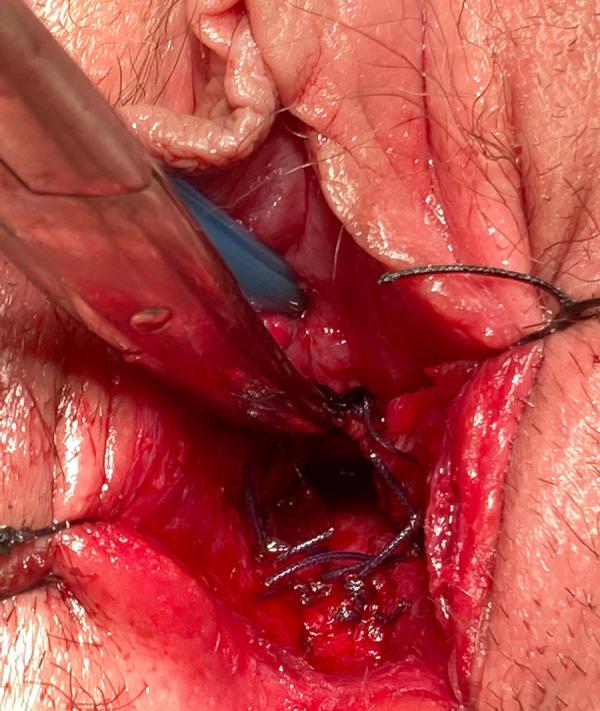

BACKGROUND Caudal regression syndrome (CRS) is a rare anomaly characterized by maldevelopment of the caudal half of the body and can involve the genitourinary system. This report presents the case of a 13-year-old girl diagnosed with CRS and previously unknown distal vaginal atresia, presenting with monthly pelvic pain. CASE REPORT A 13-year-old pre-menarcheal patient with CRS sought emergency care due to debilitating monthly pelvic pain persisting for 3 months. Pelvic examination revealed the absence of a vaginal opening, and a rectal exam showed a 5-cm large bulge anteriorly, along with a 2-cm fibrous septum in the distal portion of the vagina. Pelvic ultrasound and magnetic resonance imaging confirmed the presence of hematometrocolpus and hematosalpinx on the right adnexa, while the left ovary was not identified. Treatment commenced with fixed analgesia and combined continuous oral contraception. Due to the persistent pain and uncertainty regarding the anatomy of the internal reproductive organs, diagnostic laparoscopy with drainage of the hematocolpus was performed 2 weeks later. Six months later, after multidisciplinary discussion, definitive surgery (pull-through vaginoplasty) was carried out, allowing for emotional preparation for postoperative dilation. One year after the definitive surgery, the patient remains asymptomatic, experiencing regular withdrawal bleeding with no signs of obstruction. CONCLUSIONS Patients with musculoskeletal anomalies should undergo urogenital tract evaluation. Timely identification of distal vaginal atresia is pivotal for devising appropriate treatment and averting complications. During the acute phase, laparoscopic drainage can alleviate symptoms and clarify anatomy, without compromising the success of subsequent definitive surgery.